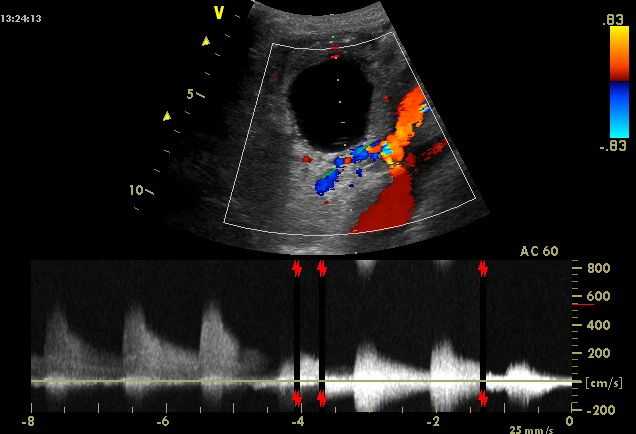

- ультразвуковая доплерография для определения степени нарушения кровотока и ишемии,